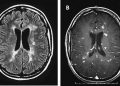

Наличие хронических активных поражений в головном мозге может дать представление о том, как быстро будут развиваться симптомы рассеянного склероза (РС). Исследователи...